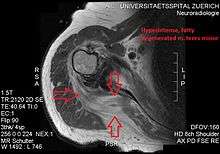

Atrophy of the teres minor muscle is often a consequence of a rotator cuff tear, but common isolated teres minor atrophies have also been found. A quadrangular space syndrome causes excessive and or chronically compression of the structures which pass through this anatomical tunnel. The axillary nerve and the posterior humeral circumflex artery pass through the space. People affected note shoulder pain and paresthesia down the arm first and foremost in abduction, extension, external rotation and overhead activity. Selective atrophy of the teres minor muscle has been seen and pulled together directly with compression of the corresponding axillary nerve branch or posterior humeral circunflex artery. Fibrous bands, cysts of the glenoid labrum, lipoma or dilated veins can occupy the quadrilateral space pathologically. Similar symptoms are common with anterior shoulder dislocation, humeral neck fracture, brachial plexus injury and thoracic outlet and inlet syndrome. It is important to include those pathologies for a complete as possible differential diagnosis.

Ultrasonography is a tool to detect a fatty degenerative atrophy of the teres minor and shows in affected muscles increased echogenicity and betimes a slight reduction in muscle bulk. MR imaging helps to consolidate the diagnosis of neurogenic muscle atrophy. Extracellular edema after traumatic events causing neural damage show an increased signal intensity on T2-weighted MRI sequences and normal intensity on T1-weighted sequences. Posterior humeral circunflex artery compression and reduced blood flow in stressful arm positions and or maneuvers can be diagnosed by a Doppler ultrasonography. The nerve should be detected adjacent to the vessel. In an elevated arm position the axillary neurovascular bundle can be seen at the posterior axillary fold just before it perforates the deltoideus, while the posterior course is well visible in the neutral position. For a detailed assessment of the artery, a MR angiography is required. The major task of an ultrasonographic examination is to rule out any space occupying mass. Additional electromyography is helpful to reveal any decelerated nerve conduction velocity, and thus denervation of the concerned muscle.[6]